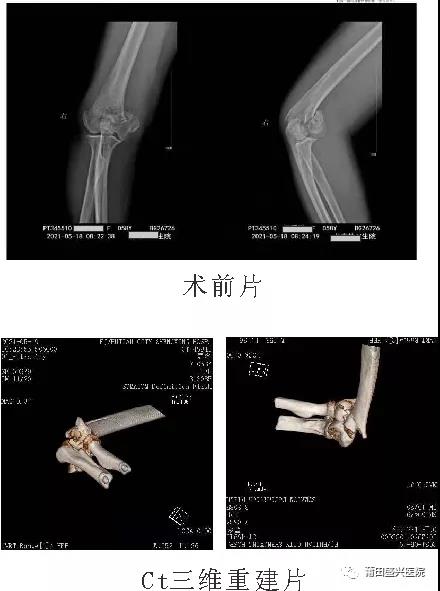

日前,有一女性患者王xx,右肱骨髁間粉碎性骨折,經(jīng)過與家屬及本人溝通后,我院業(yè)務(wù)副院長……